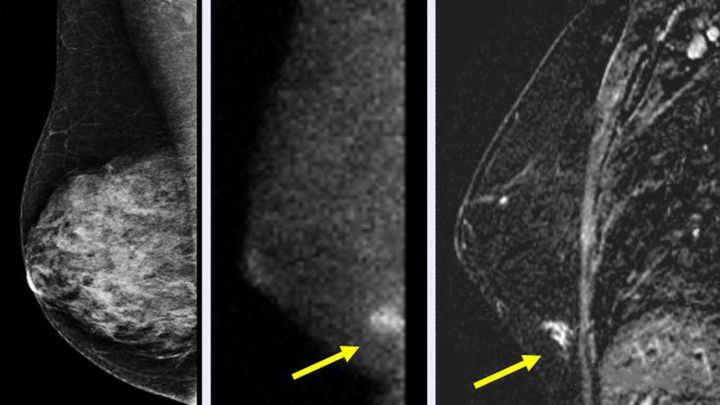

1. 乳腺X线(钼靶)检查:该检查简便易行,对降低40岁以上妇女乳腺癌死亡率效果明显。但乳腺X线对年轻致密乳腺策划穿透力差,故一般不建议对40岁以下、无明确乳腺癌高危因素或临床体检未发现异常的妇女进行乳腺X线检查。常规乳腺X线检查的射线剂量低,不会危害妇女健康,但正常女性无需短期内反复进行乳腺X线检查。

而且这个检查不用担心“飞机场”没法拍摄钼靶,放射科医生会想办法让无论是半球形还是锥形的乳房在检查仪器上就位的。以下显影结果都是乳腺癌患者癌肿的影像。

图片来源网络,侵删!